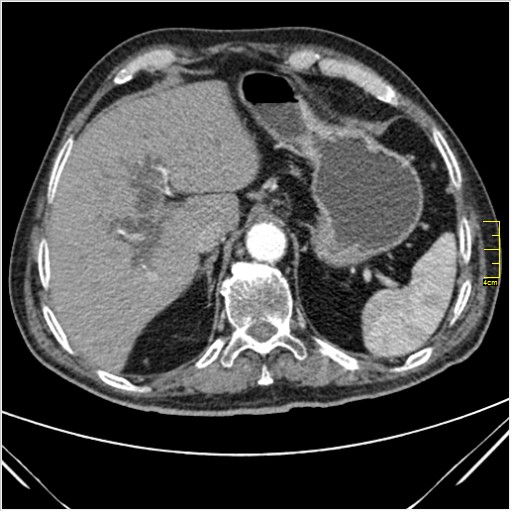

Мужчина 62 года с желтухой

Опухоль головки поджелудочной железы, расширение холедоха и панкреат. протока (Double Channel sign)

Карциномы панкреас гиподенсны на КТ с болюсом, т.к. содержать много соединительной и фиброзной ткани, в отличие от нормальной ткани железы, которая (как любая железа) хорошо васкуляризирована. Поэтому если видим в панкреас солидное гиподенсное образование - всегда настораживает на предмет рака. Второй момент: обязательная оценка взаимоотношения опухоли к ВБА и ВБВ, на предмет оценки операбельности.